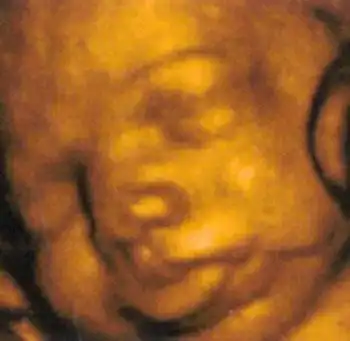

Создатель этой системы профессор Стюарт Кэмпбелл, один из ведущих акушеров Соединенного Королевства, стал знаменитостью в мире медицины благодаря снимкам, на которых зародыш улыбается (раньше считалось, что эта способность появляется лишь после рождения)...

12-я неделя. Оформились веки, мочки ушей, на пальчиках уже растут ноготки. Ребенок морщит губы, открывает и закрывает рот, может всасывать и глотать жидкость, которая его окружает.